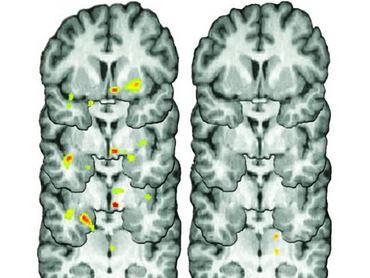

A vizsgálat során 35 emberen végeztek el agyi CT-t – közülük 17-en depressziósak voltak. Az alanyoknak különböző profilok közül kellett kiválasztaniuk, hogy kivel randiznának, majd utána közölték velük, hogy az illető elutasította őket. A depresszióban nem szenvedő emberek agya természetes fájdalomcsillapítókat (ópiátokat) bocsátott ki válaszul, míg a betegségben szenvedőké csak sokkal kisebb adagot termelt a fehérjékből.

(A képen a sárga és a piros területekkel jelezték a termelődés helyét.) Érdekes eredmény volt az is, hogy a visszautasítás után a depressziósok sokkal kisebb érdeklődést mutattak az iránt, hogy másokkal is megismerkedjenek. "A közösségi stresszorok fontos szerepet játszanak a betegségek, például a depresszió, a szorongás vagy más neuropszichiátriai esetek javulásában vagy rosszabbodásában" – állapította meg dr. Jon-Kar Zubieta, a tanulány egyik szerzője.